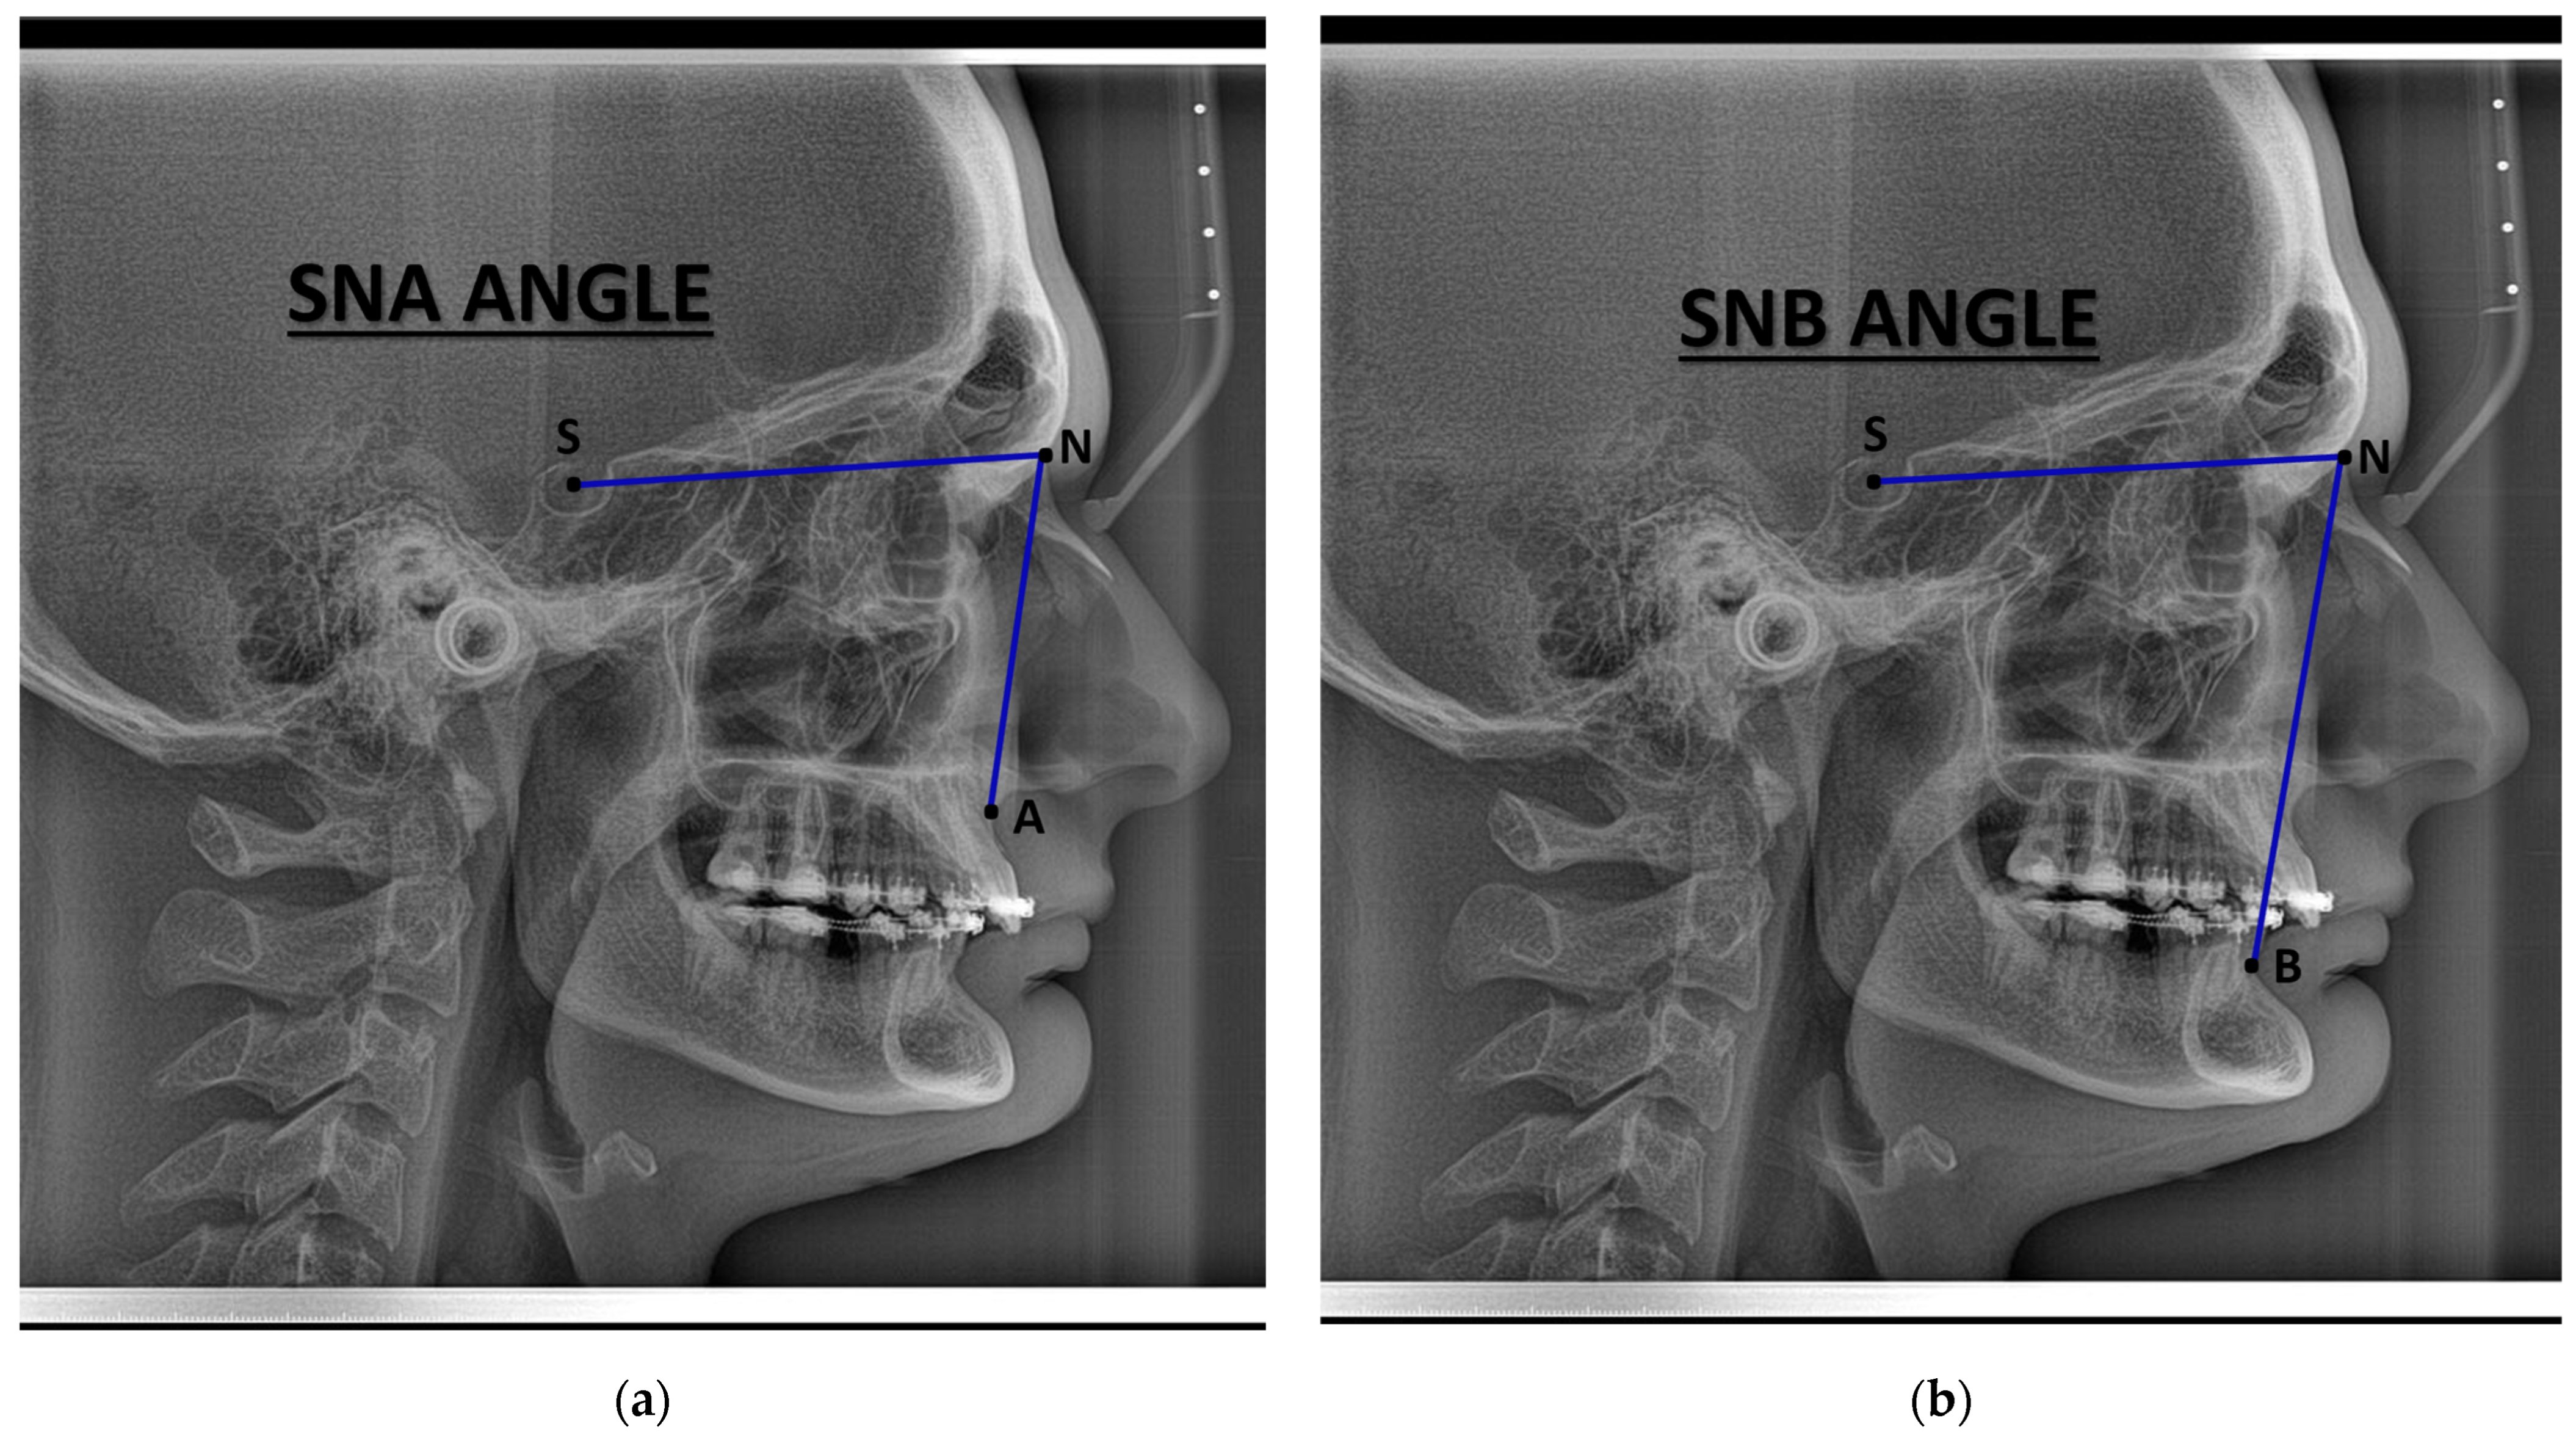

| Characteristic | Preoperative Median (IQR) | Postoperative Median (IQR) |

|---|---|---|

| Demographics | ||

| Age (years) | 28.0 (24.0, 33.0) | – |

| Sex, n (%) | Female: 11 (44%) Male: 14 (56%) | – |

| Skeletal parameters | ||

| SNA (°) | 83.6 (79.9, 84.9) | 86.3 (80.4, 89.0) |

| SNB (°) | 83.5 (76.8, 87.2) | 84.0 (81.0, 86.0) |

| ANB (°) | 0.9 (−4.9, 5.3) | 3.0 (−0.2, 4.5) |

| Pogonion to N-Perpendicular FH (mm) | 1.87 (−0.94, 2.31) | 1.4 (0.4, 2.6) |

| Dental parameters | ||

| U1–NA (°) | 26 (21, 28) | 22 (19, 29) |

| L1–NB (°) | 24 (17, 27) | 25 (19, 30) |

| Soft tissue parameters | ||

| Nasolabial angle (°) | 102 (92, 114) | 105 (91, 117) |

| Facial convexity (°) | 0 (−12, 7) | 2 (−6, 5) |

| Variable | Mean Difference | SE Difference | t | df | p-Value |

|---|---|---|---|---|---|

| SNA (°) | −3.123 | 1.24 | −2.511 | 24 | 0.019 |

| SNB (°) | −1.147 | 1.41 | −0.811 | 24 | 0.426 |

| ANB (°) | −1.980 | 1.00 | −1.977 | 24 | 0.060 |

| Pogonion to N-Perpendicular FH (mm) | −1.571 | 1.21 | −1.296 | 24 | 0.207 |

| U1–NA (°) | 0.465 | 1.87 | 0.249 | 24 | 0.806 |

| L1–NB (°) | −2.968 | 1.55 | −1.915 | 24 | 0.067 |

| Nasolabial angle (°) | −6.950 | 8.83 | −0.787 | 24 | 0.439 |

| Facial convexity (°) | −0.502 | 4.12 | −0.122 | 24 | 0.904 |